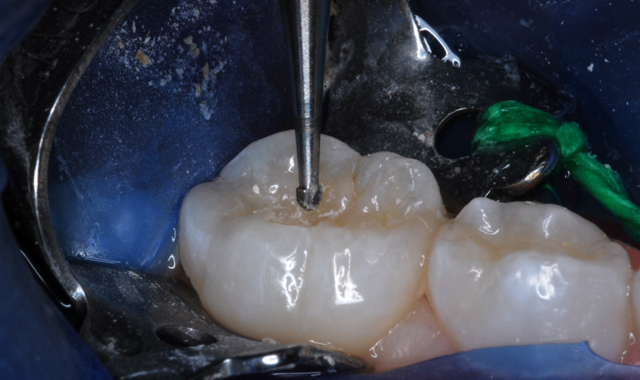

Fig. 3 Fig. 4

After appropriate local anesthesia, the tooth was isolated with a rubber dam, using the “slit dam” method (Fig. 2). Outline form was prepared using a high-speed diamond bur, exposing the extent of the caries lesion (Fig. 3). Carious dentin was debrided with slow-speed round burs and the cavity preparation was completed (Figs. 4 and 5).